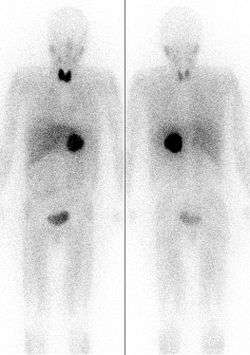

Of the many isotopes of iodine, only two are typically used in a medical setting: iodine-123 and iodine-131. Since 131I has both a beta and gamma decay mode, it can be used for radiotherapy or for imaging. 123I, which has no beta activity, is more suited for routine nuclear medicine imaging of the thyroid and other medical processes and less damaging internally to the patient. There are some situations in which iodine-124 and iodine-125 are also used in medicine.[4]

Due to preferential uptake of iodine by the thyroid, radioiodine is extensively used in imaging of and, in the case of 131I, destroying dysfunctional thyroid tissues. Other types of tissue selectively take up certain iodine-131-containing tissue-targeting and killing radiopharmaceutical agents (such as MIBG). Iodine-125 is the only other iodine radioisotope used in radiation therapy, but only as an implanted capsule in brachytherapy, where the isotope never has a chance to be released for chemical interaction with the body's tissues.

Iodine-124 as the iodide salt can be used to directly image the thyroid using positron emission tomography (PET).[7] Iodine-124 can also be used as a PET radiotracer with a usefully longer half-life compared with fluorine-18.[8] In this use, the nuclide is chemically bonded to a pharmaceutical to form a positron-emitting radiopharmaceutical, and injected into the body, where again it is imaged by PET scan.

) is a beta-emitting isotope with a half-life of eight days, and comparatively energetic (190 keV average and 606 keV maximum energy) beta radiation, which penetrates 0.6 to 2.0 mm from the site of uptake. This beta radiation can be used for the destruction of thyroid nodules or hyperfunctioning thyroid tissue and for elimination of remaining thyroid tissue after surgery for the treatment of Graves' disease. The purpose of this therapy, which was first explored by Dr. Saul Hertz in 1941,[9] is to destroy thyroid tissue that could not be removed surgically. In this procedure, 131I is administered either intravenously or orally following a diagnostic scan. This procedure may also be used, with higher doses of radio-iodine, to treat patients with thyroid cancer.

The 131I is taken up into thyroid tissue and concentrated there. The beta particles emitted by the radioisotope destroys the associated thyroid tissue with little damage to surrounding tissues (more than 2.0 mm from the tissues absorbing the iodine). Due to similar destruction, 131I is the iodine radioisotope used in other water-soluble iodine-labeled radiopharmaceuticals (such as MIBG) used therapeutically to destroy tissues.